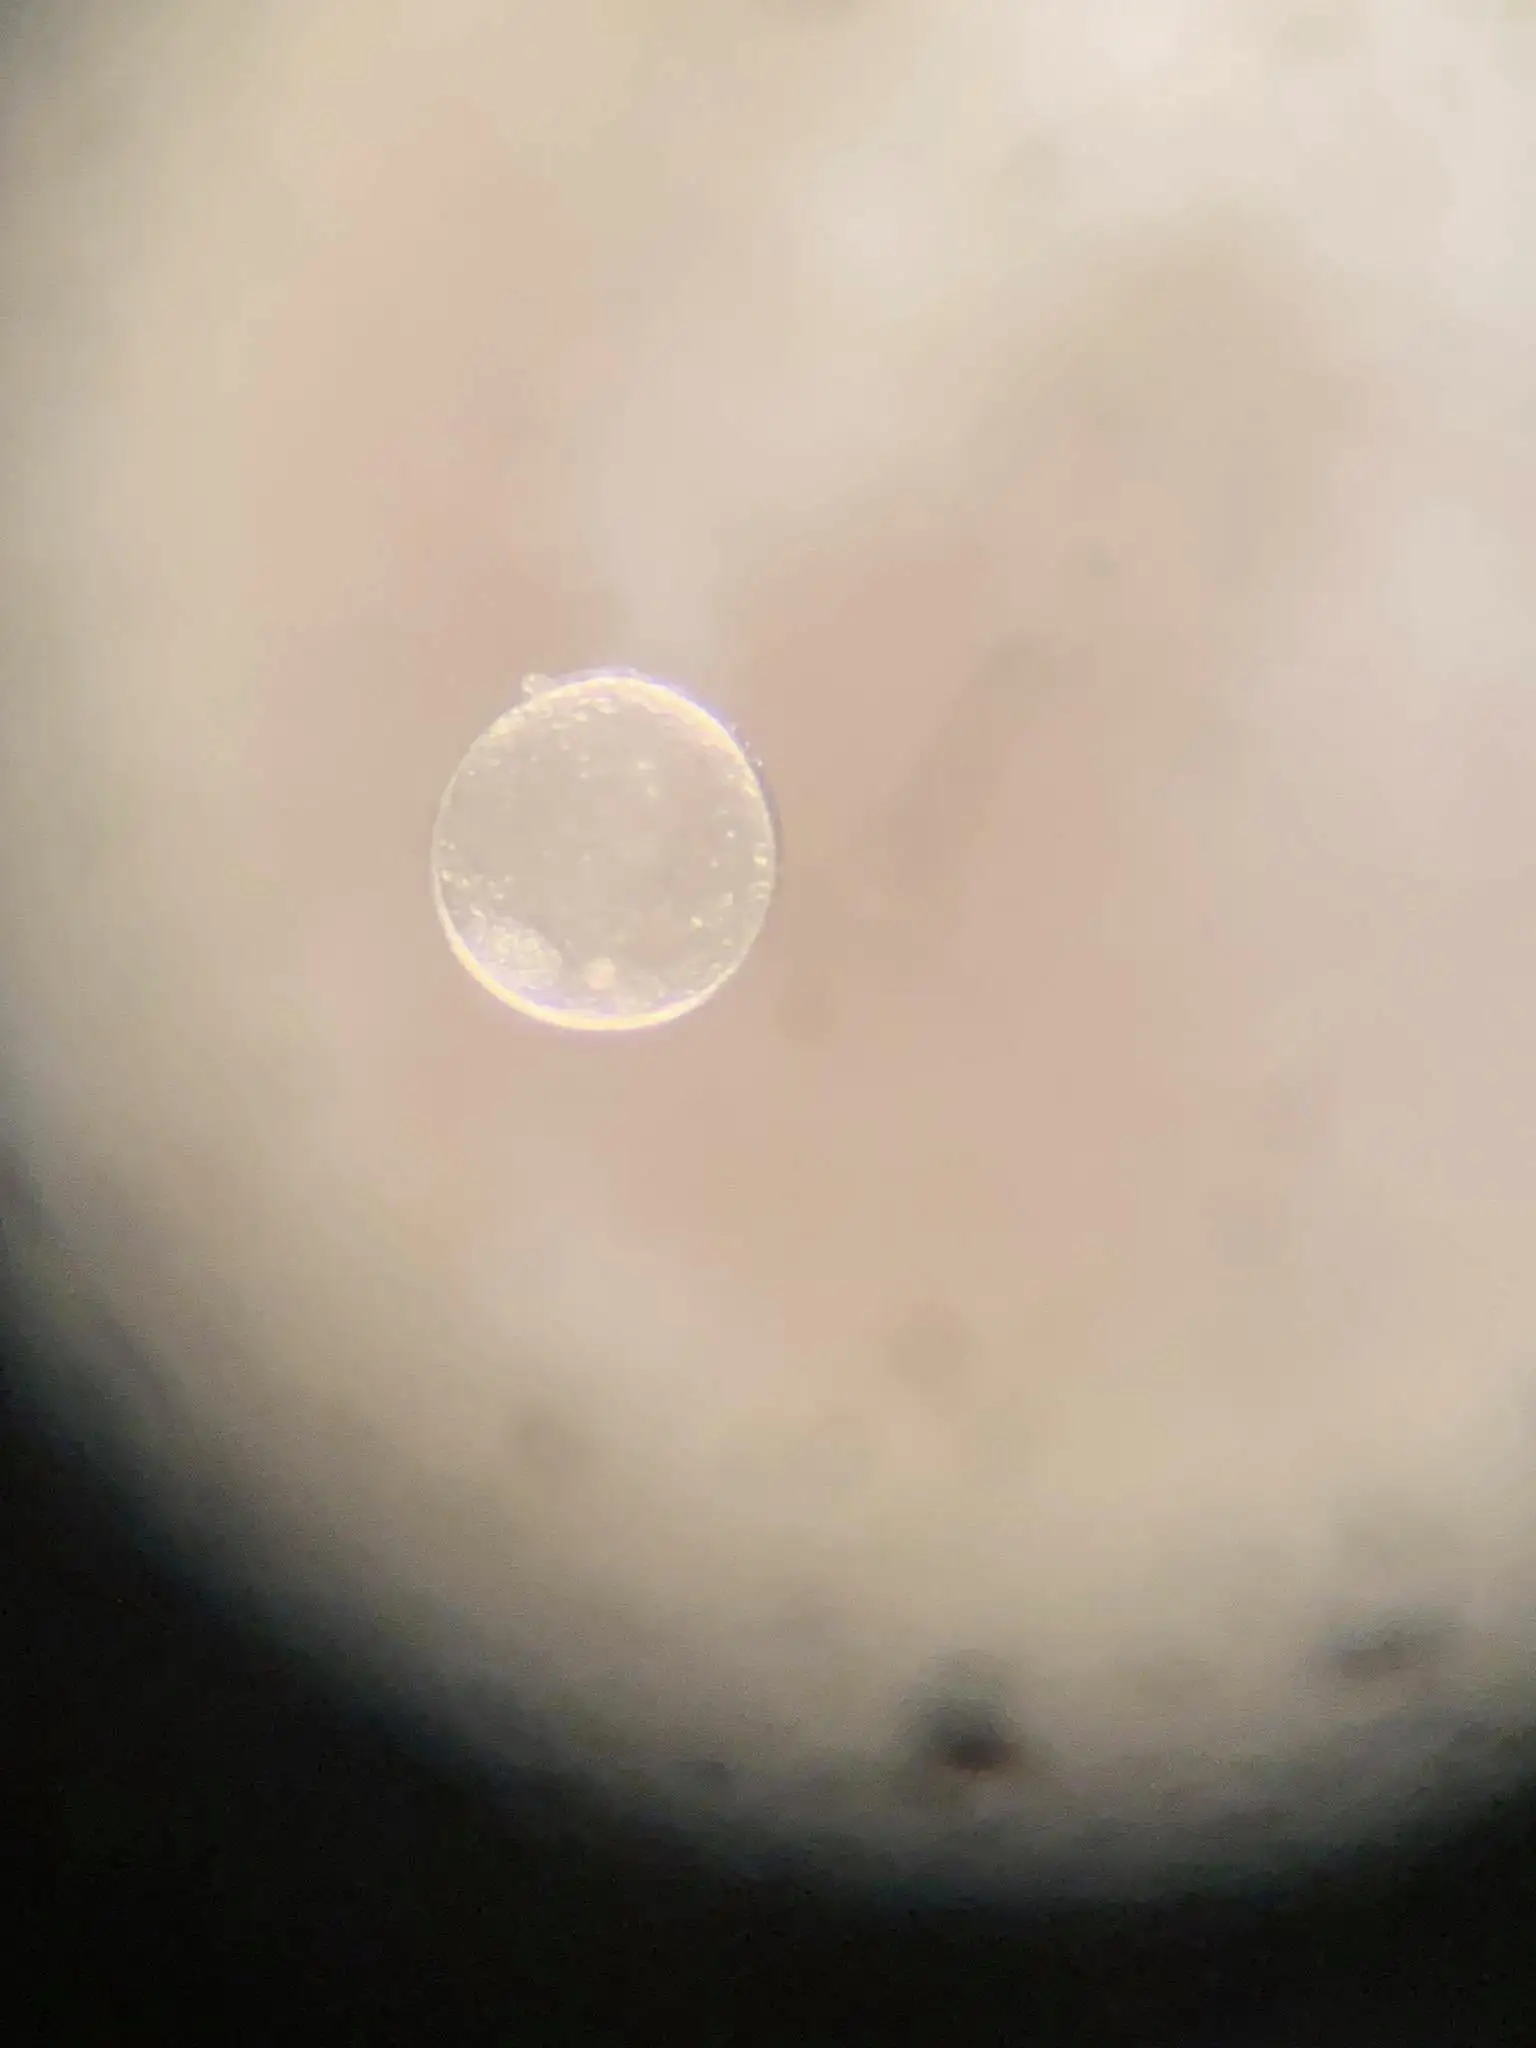

Our digital x-ray and ultrasonography capabilities are second to none, ensuring the best results for diagnosis and prognosis in most cases. Cases ranging from reproductive to medical benefit from both our modern equipment and wide-ranging experience.